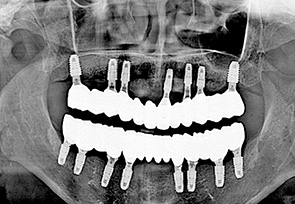

전악 임플란트는 치아가 완전히 없는 상태라도 잇몸뼈가 남아 있다면 임플란트를 여러개 심어 고정식으로 이를 해 넣을 수 있습니다. 잇몸 뼈에 단단히 고정되는 임플란트를 이용한 치료법으로 틀니를 사용할 때 보다 힘이 훨씬 좋고 내 치아 처럼 사용할 수 있습니다. 자연치아는 모두 28개 이지만 실직적으로 자연치아 개수만큼 다 심을 필요는 없습니다. 고정성 전악 임플란트를 위해서는 위 아래 턱 뼈와 맞물리게 되는 치아의 상태와 잇몸 뼈의 상태 등을 고려하여 임플란트를 식립하게 되며 보통 아래는 6~7개, 위에는 7~8개의 임플란트를 식립한 후 고정식으로 보철물을 결합하게 됩니다.

치료 케이스 보기

• after